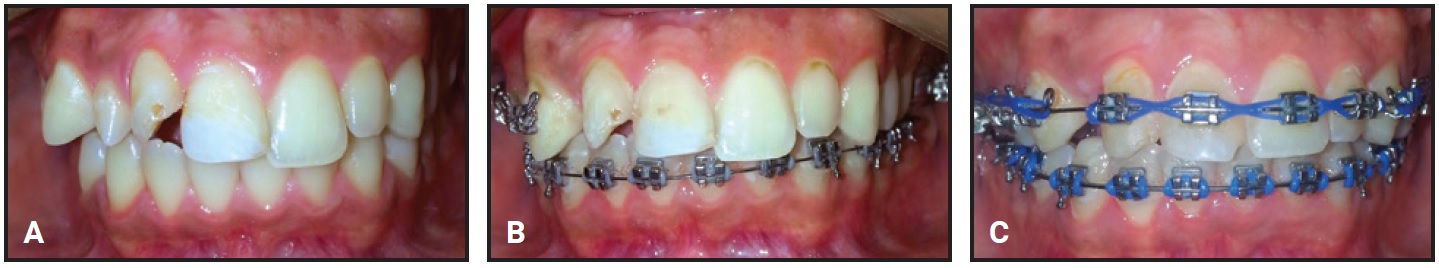

Two weeks later, the Herbst arms were attached to the laser-soldered nuts of the miniplates (Fig. 3).

Fig. 3 A. Before attachment of MiniScope Herbst* arms. B. After Herbst placement.

The appliance did not cause any ulceration during treatment. The left MiniScope was removed after seven months to help resolve the dental midline discrepancy. The right MiniScope was removed three months later, when the profile had improved and a dental Class I relationship had been achieved (Fig. 4). The lower incisor inclination was unchanged.